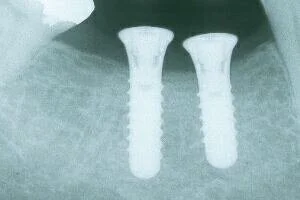

Aurora Periodental Centre does most of the implant surgery for Dr. Ehrlich’s patients, and you can visit their website for more information. In some simpler cases, Dr. Ehrlich places the implants right in this office. Dr. Ehrlich restores the teeth on the implants. Once the implants are in place, all the rest of the dentistry is just “nuts and bolts"- no drilling, noise or anaesthetic involved. (Photos below show the before, during, and after of 2 implants by x-ray, as well as photos of the temporary caps and the finished product!)

implant_postop_pa.JPG

Teeth on the implants